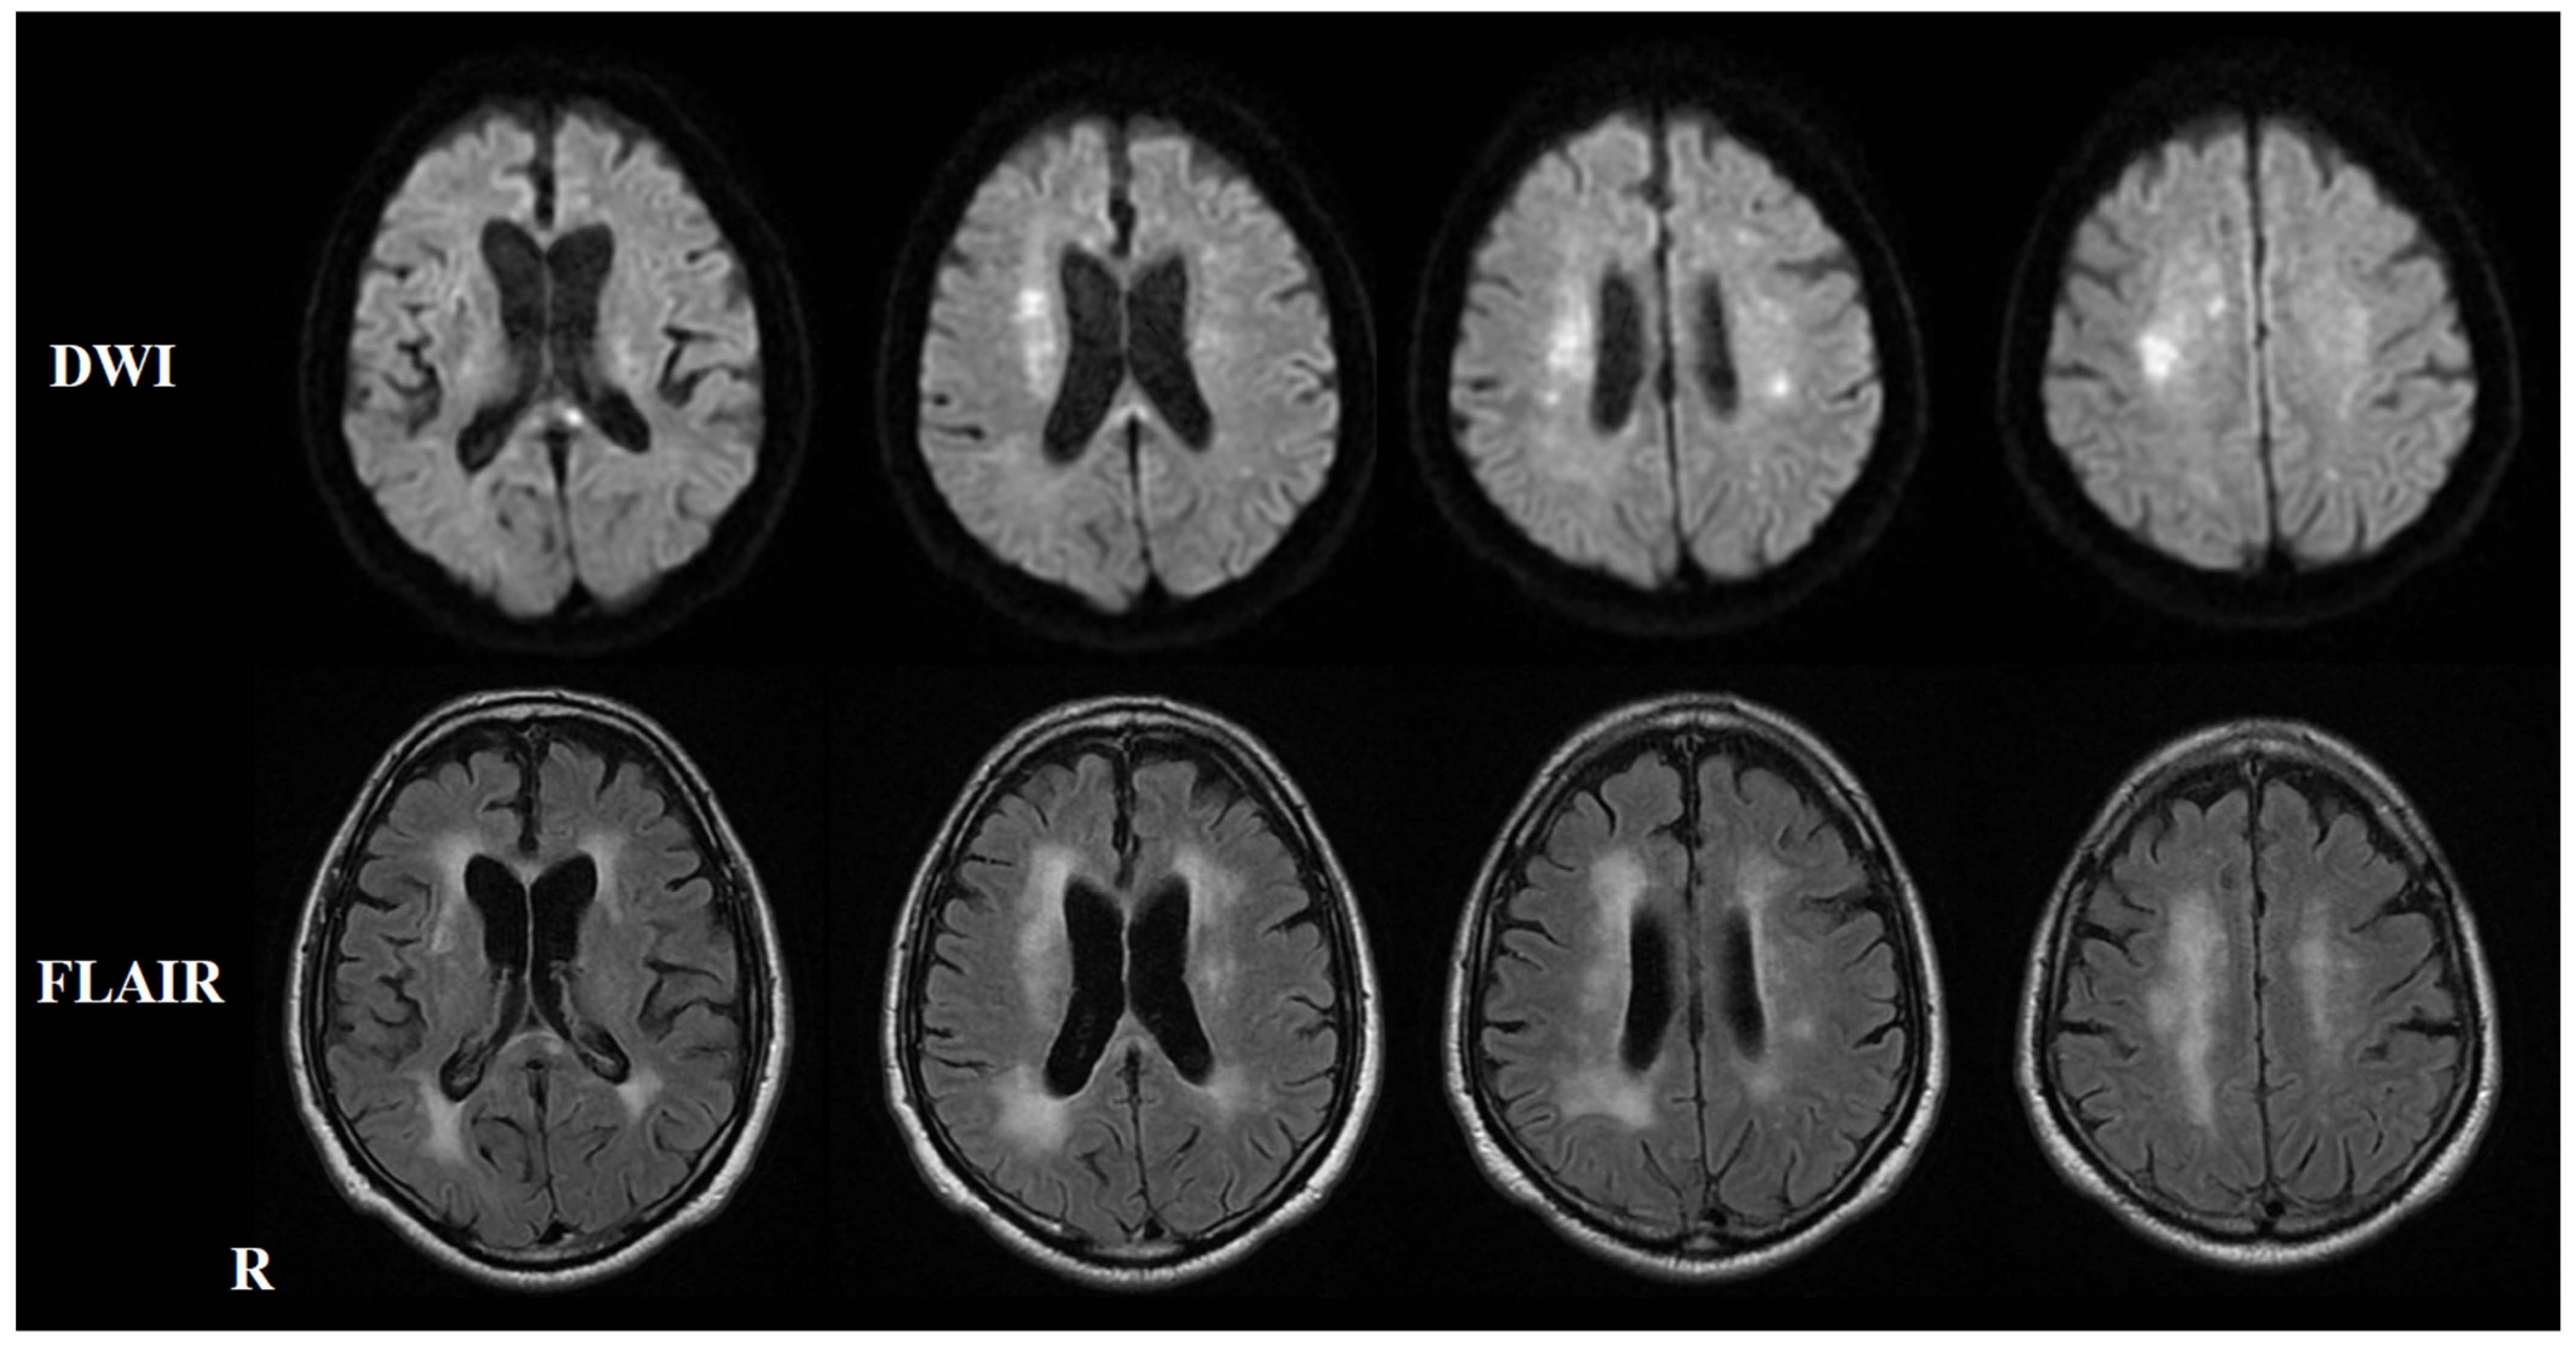

2. Case Presentation